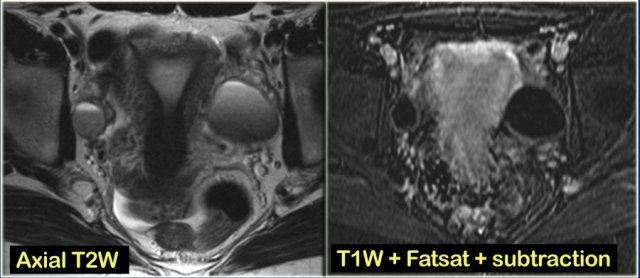

6 months later a follow-up MRI was performed.

The lesions are bright on T1-weighted images.

The bright signal persists on fat saturation indicating the presence of blood.

There is T2 shading consistent with a hemorrhagic lesion.

There is no enhancement.

The fluid-fluid level in the right ovarian lesion also confirms its cystic nature.

The fact that the lesions persist after 6 months makes bilateral endometrioma much more likely than hemorrhagic cysts.